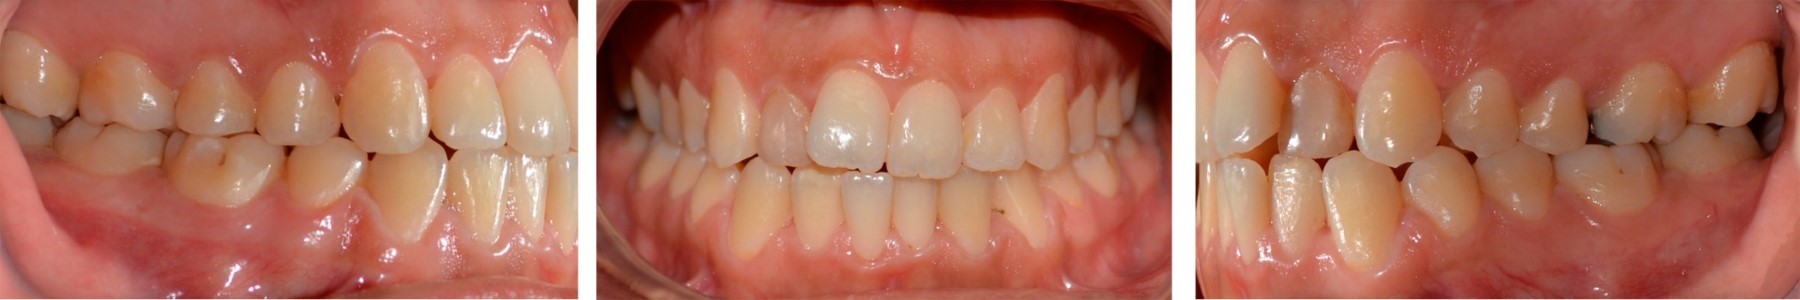

La duración del tratamiento fue de 32 meses, se alcanzó la coordinación de ambas arcadas, se corrigió el exceso de crecimiento vertical de la paciente, se consiguió clase I canina bilateral, sonrisa con arco positivo, correcta guía anterior (overjet y overbite), coincidencia de las líneas medias, se eliminó la mordida borde a borde en sector anterior y la mordida cruzada en sector posterior derecho (Figuras 5 y 6). En el examen radiográfico se observó paralelismo radicular y las adecuadas inclinaciones de los incisivos (Figuras 7 y 8, Tabla 2).